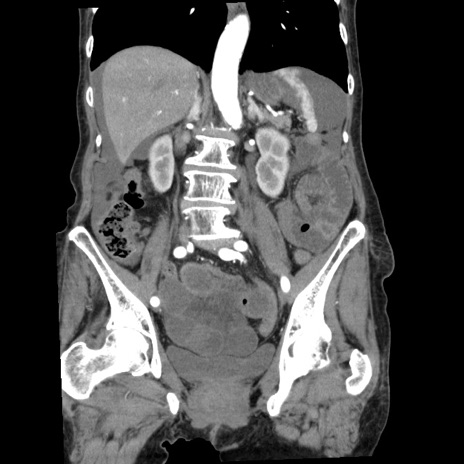

症例1(冠状断像)

【症例】80歳代女性

【主訴】腹痛

【現病歴】8時間前から腹痛あり来院。

【既往歴】糖尿病、脂質異常症、子宮体癌にて子宮全摘術

【身体所見】意識清明・会話良好だが腹痛で苦悶様、全腹部にわたって反跳痛と圧痛あり

【データ】WBC 13600、CRP 0.14、LDH 224、CK 90